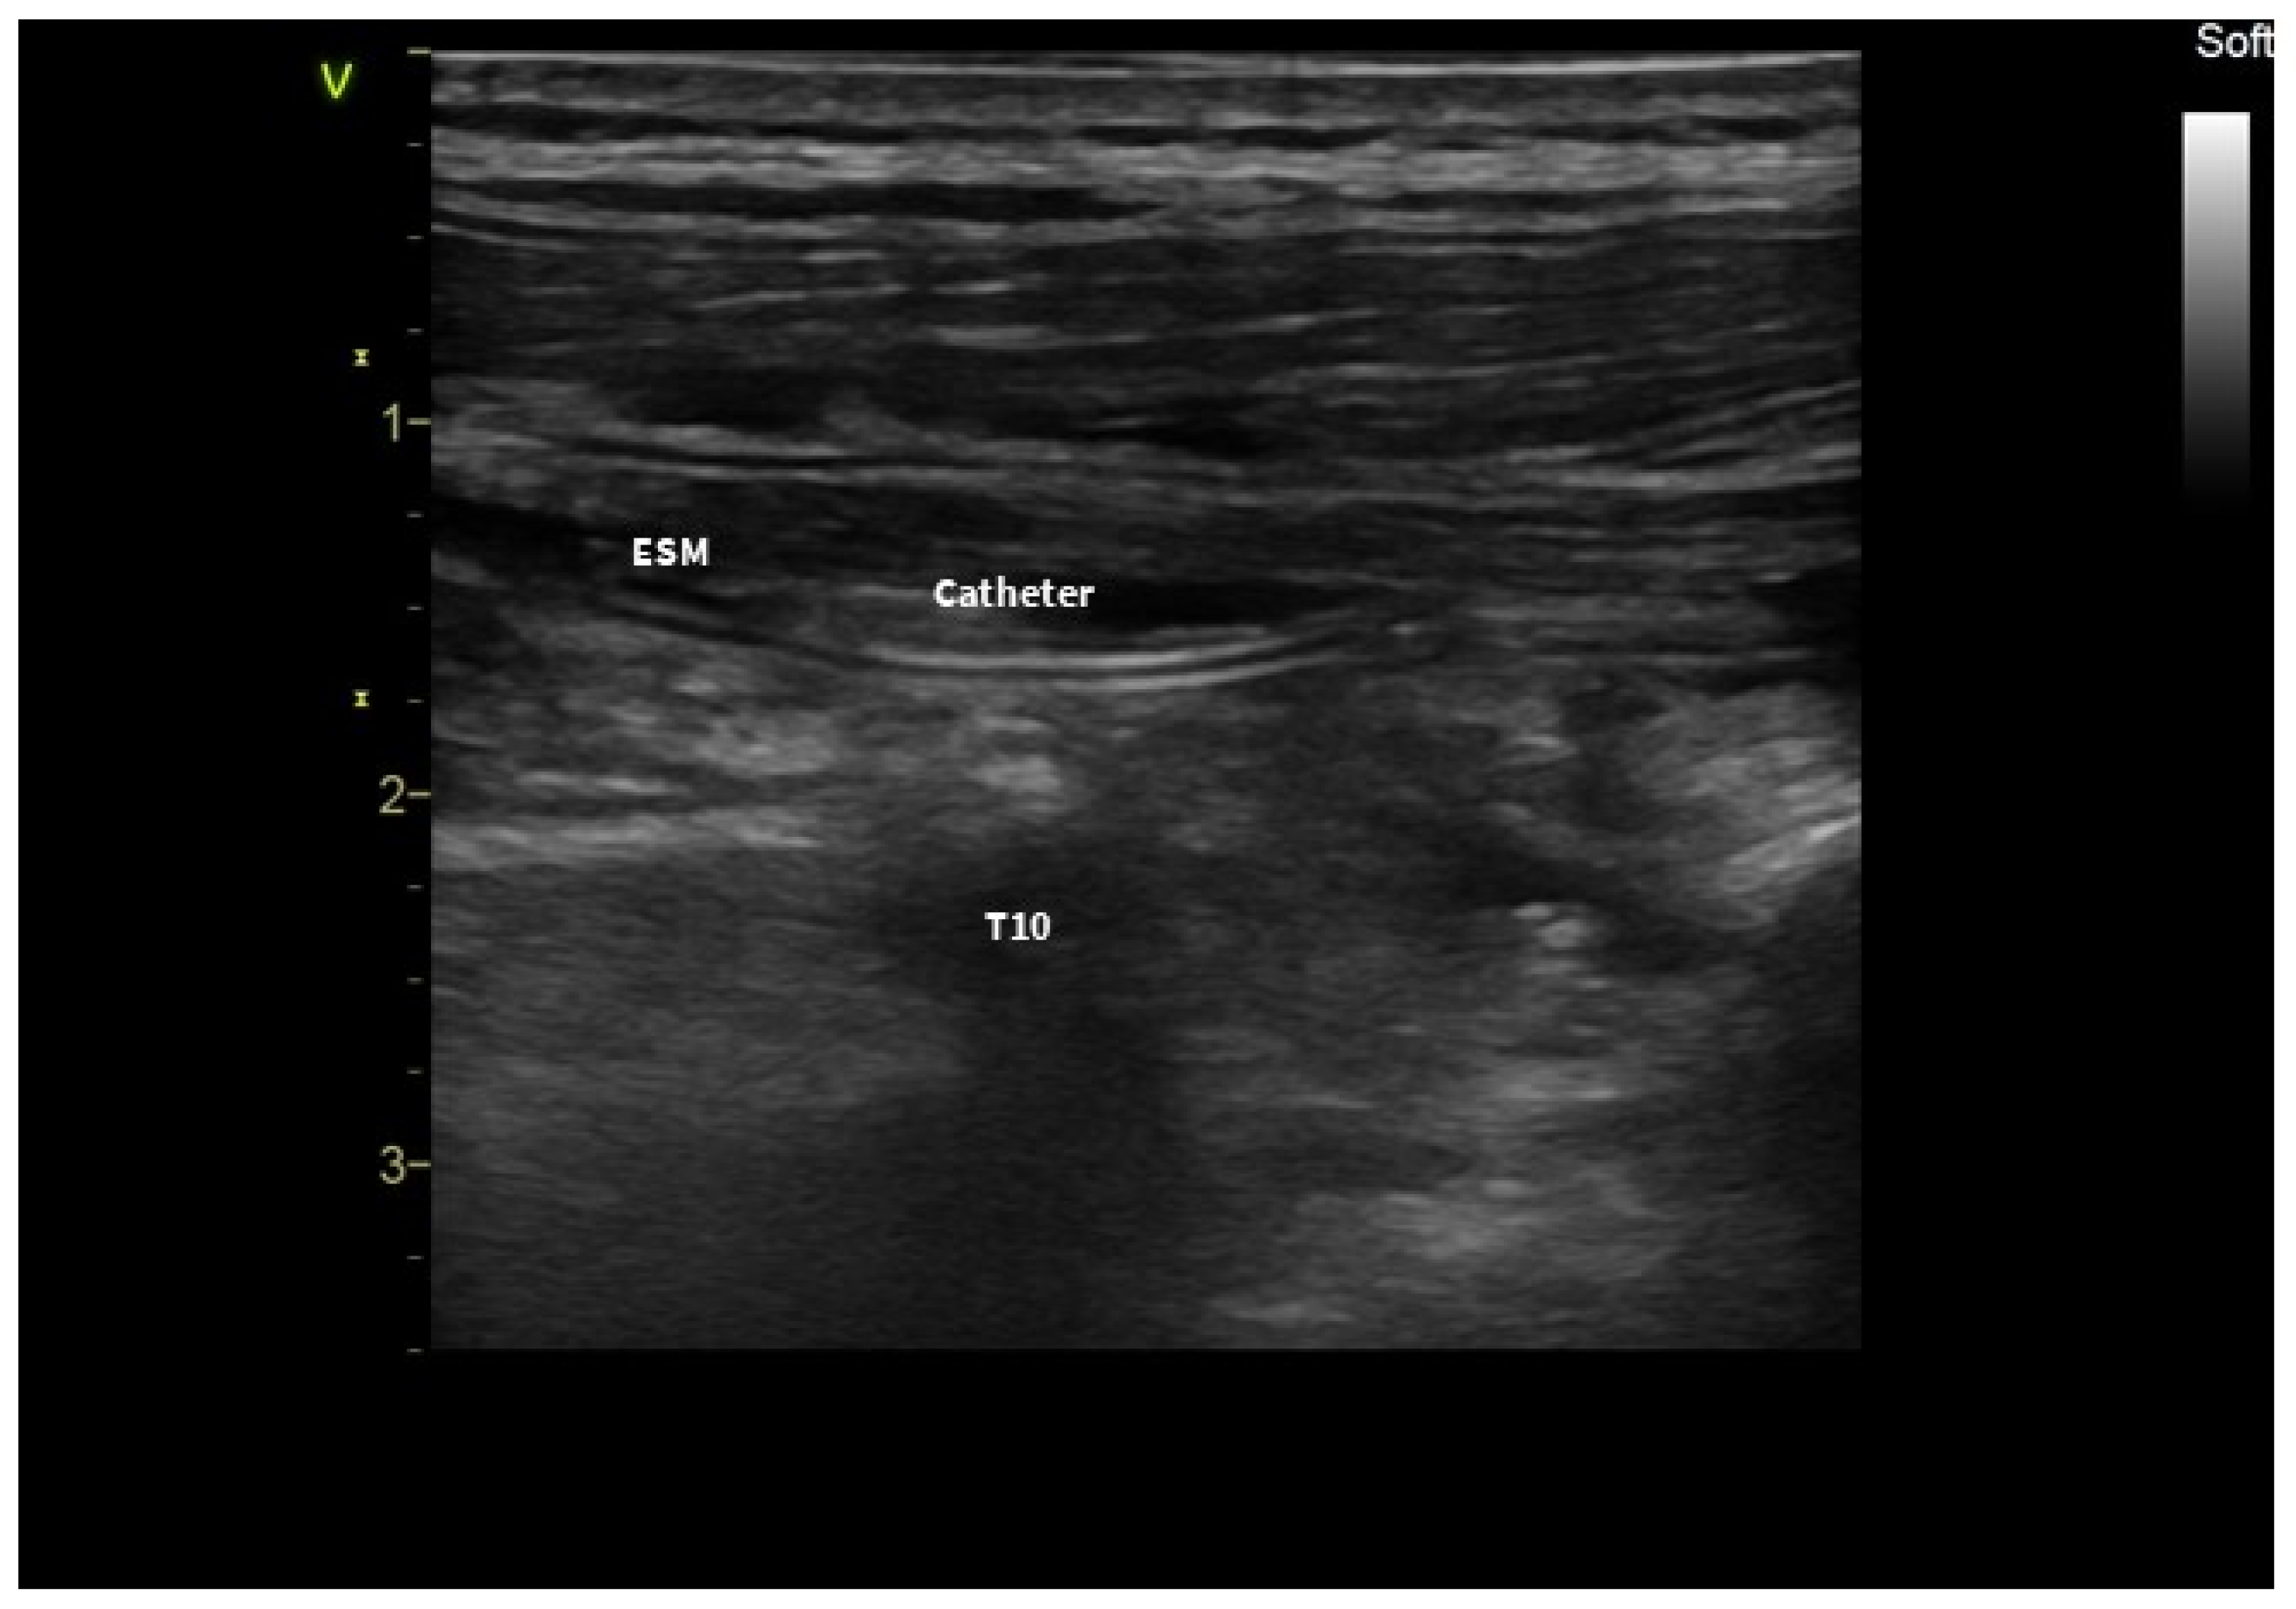

2. Case Presentation